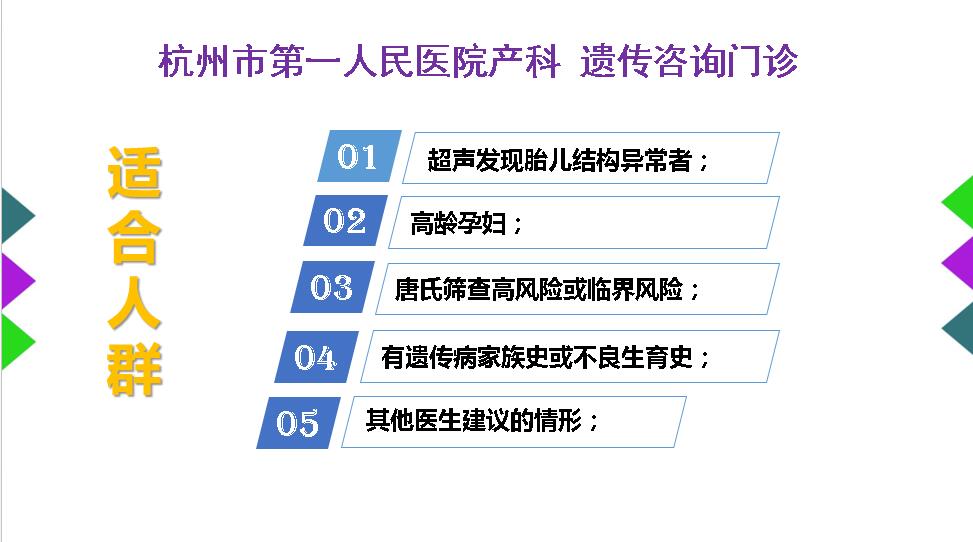

3. 遗传咨询门诊

为产前筛查高风险孕妇提供咨询和产前诊断服务。

预约挂号://guahao.zjol.com.cn/department/0571057101/1502